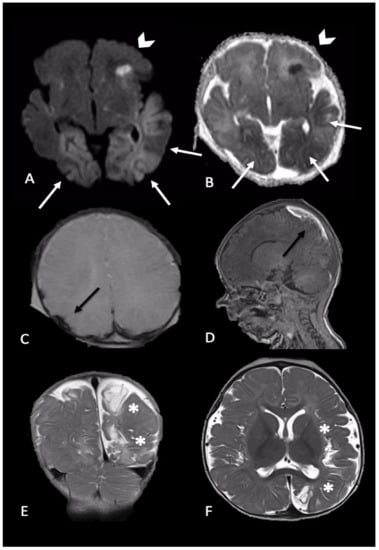

2.2. Parenchymal Injury

2.3. Spinal Injury